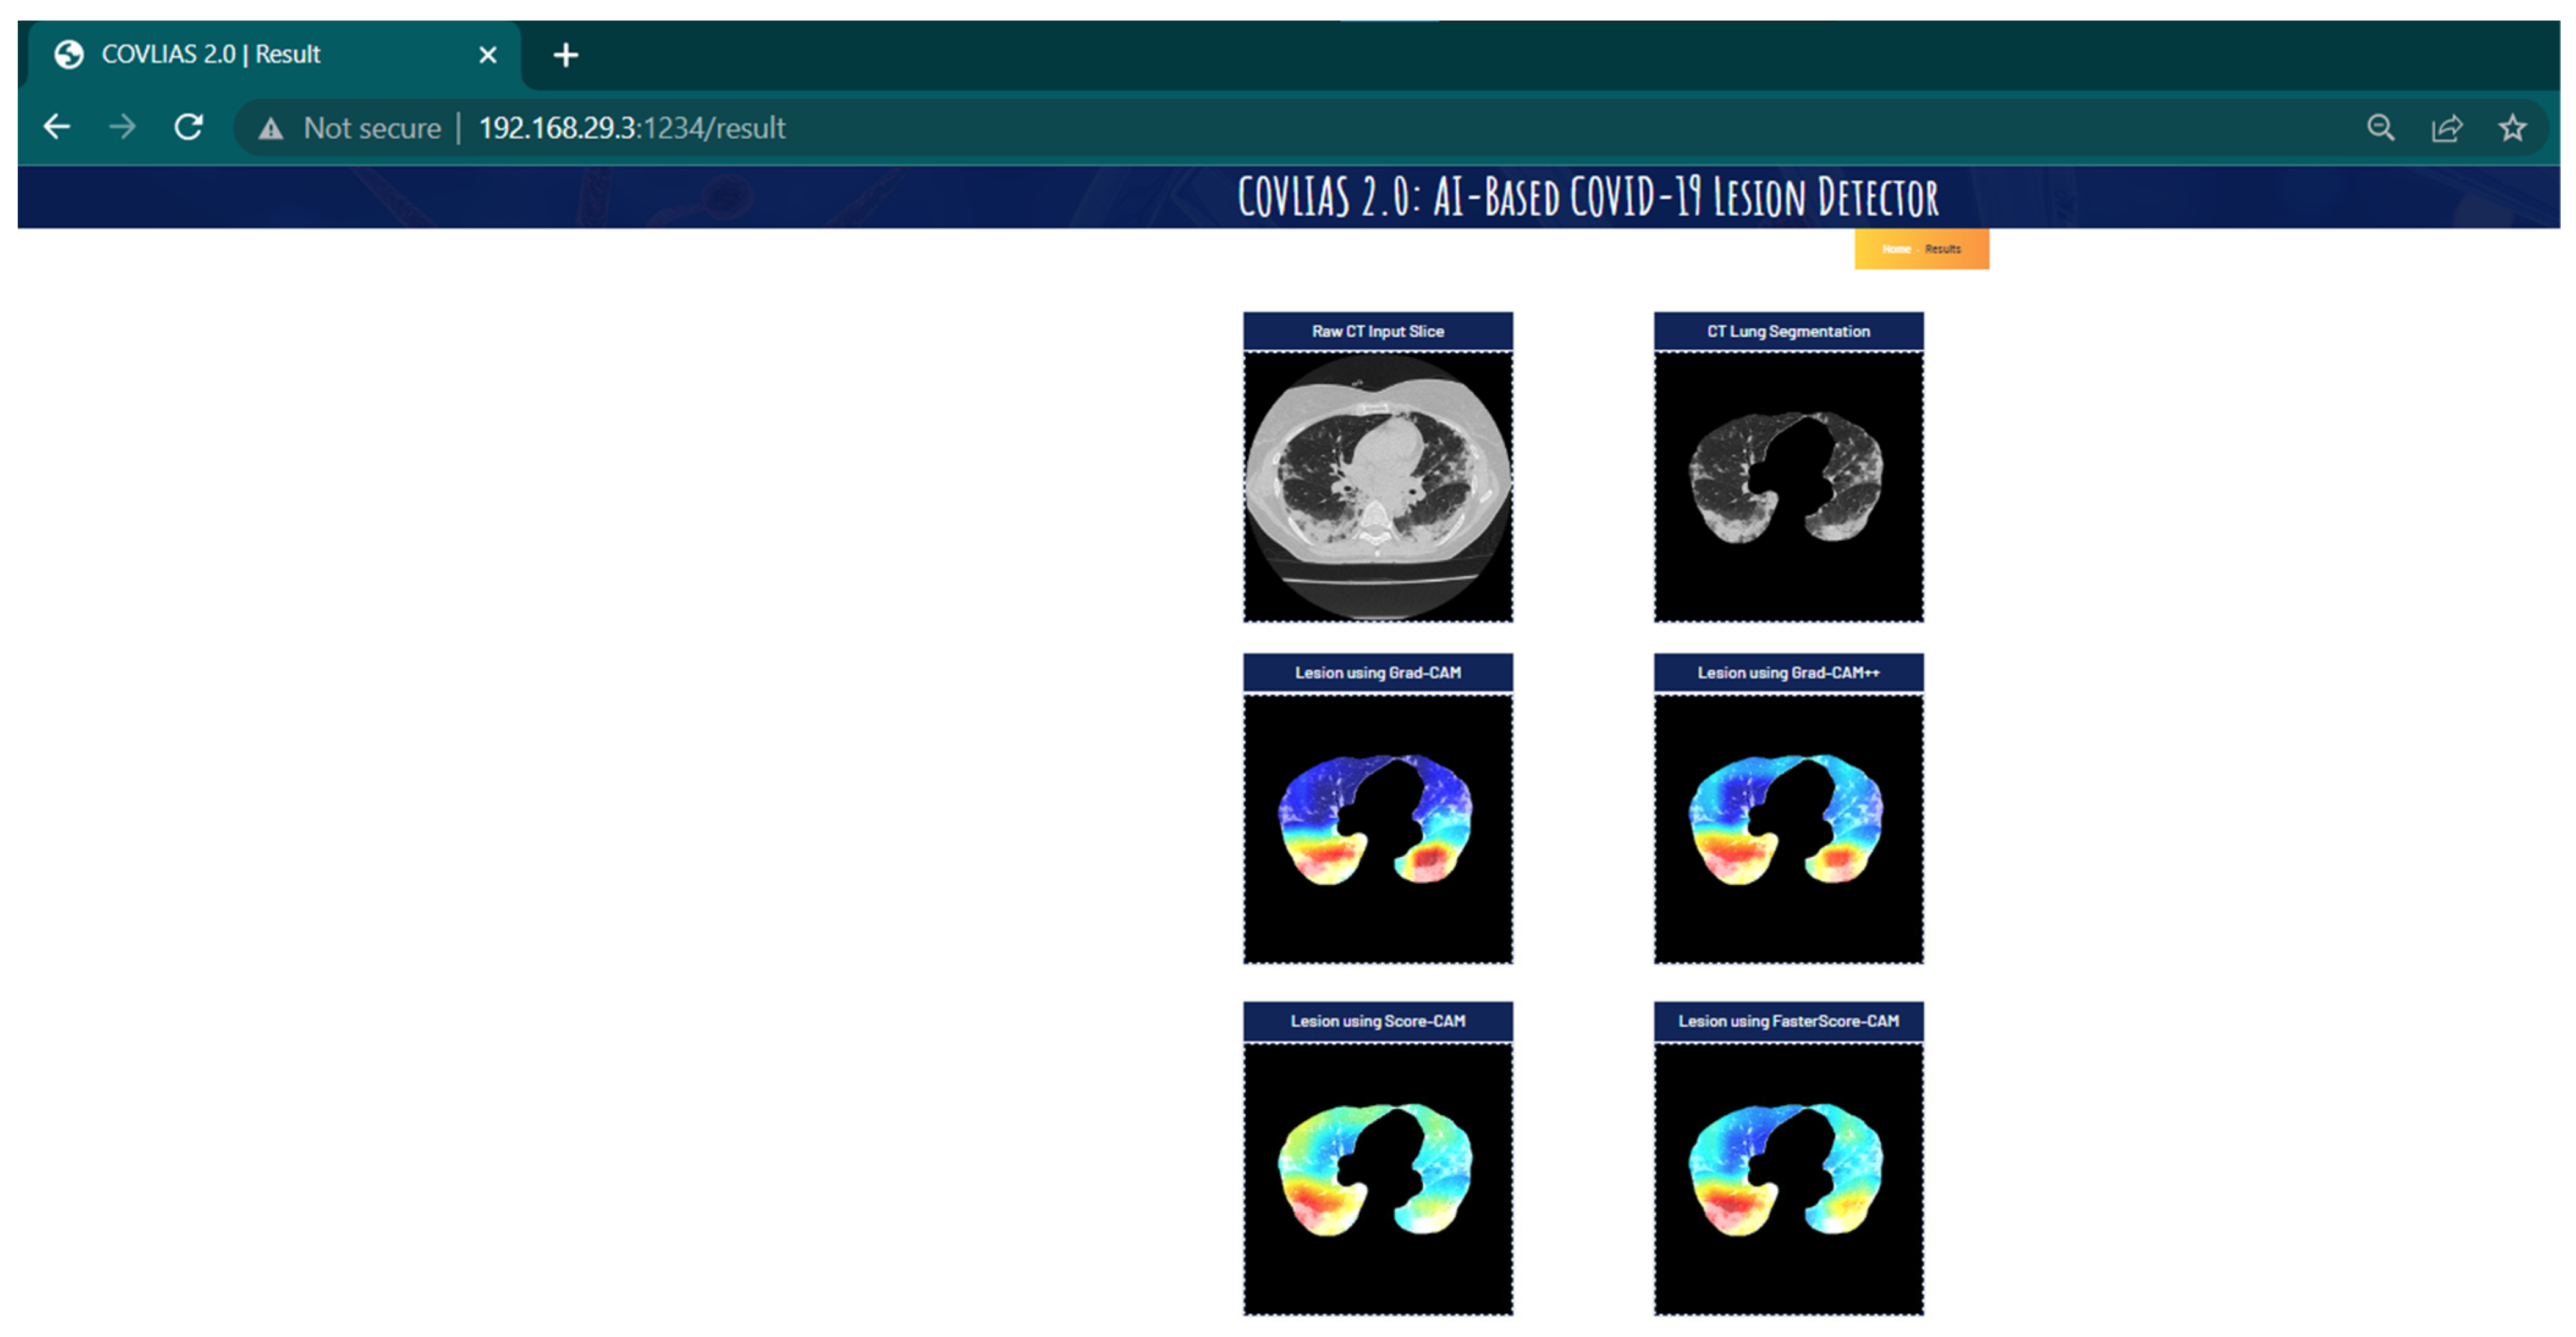

Visual Results Representing Lesion Using the Four CAM Techniques